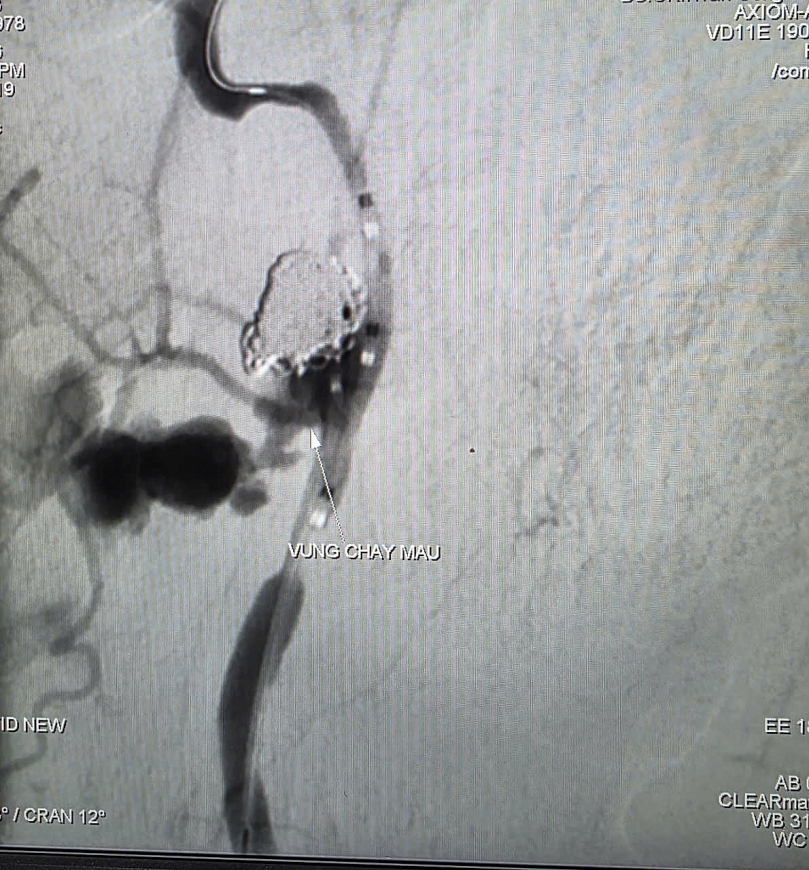

Hình ảnh thoát mạch của bệnh nhân trước can thiệp

Kết quả CT Scan cho thấy khối tổn thương choán chỗ tại khoang niêm mạc hầu lệch phải, đã xâm lấn vào động mạch cảnh trong, kèm dấu hiệu thoát thuốc cản quang ra vùng hầu họng lân cận và hình thành ổ giả phình động mạch cảnh trong dưới nền sọ – nguyên nhân gây xuất huyết ồ ạt.

Kết quả chụp mạch xác định ổ giả phình động mạch cảnh trong phải đoạn cổ, dưới nền sọ, kích thước 4,2 x 4,8 mm, cổ túi phình rộng và đang chảy máu.